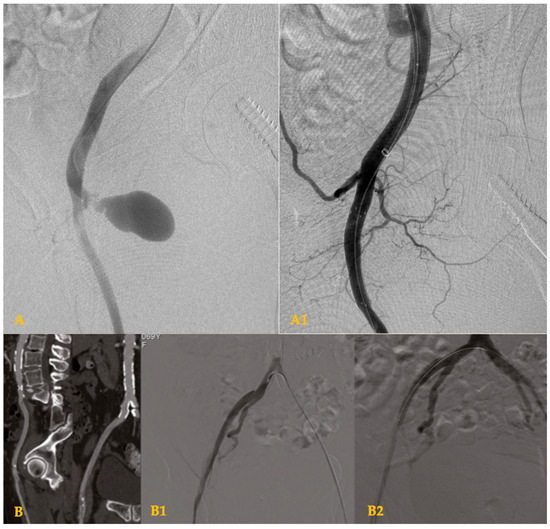

Reverse-Wire TEVAR for Subacute Type B Aortic Dissection with Severe True-Lumen Collapse: A Case Report

Type B aortic dissection (TBAD) requires management tailored to the disease phase and clinical presentation, with the subacute period representing a favorable window for endovascular intervention due to improved procedural safety and remodeling potential. We report the case of a 38-year-old male with [...] Read more.

Type B aortic dissection (TBAD) requires management tailored to the disease phase and clinical presentation, with the subacute period representing a favorable window for endovascular intervention due to improved procedural safety and remodeling potential. We report the case of a 38-year-old male with hypertension, dyslipidemia, and bicuspid aortic valve disease who presented one month after symptom onset with persistent chest pain and progressive bilateral lower-limb numbness. Clinical examination suggested early spinal cord ischemia, while laboratory tests demonstrated acute hepatic and renal dysfunction. CT angiography revealed a subacute TBAD with a markedly expanded false lumen and near-complete compression of the true lumen, resulting in visceral, renal, and potential spinal malperfusion. Given the high-risk anatomy and evolving organ dysfunction, a staged hybrid strategy was undertaken. A left carotid–subclavian bypass was performed to secure proximal landing for endovascular repair, followed the next day by thoracic endovascular aortic repair (TEVAR) using two thoracic stent grafts. Postoperative recovery was favorable, with rapid resolution of neurological symptoms and normalization of hepatic and renal parameters, allowing discharge on postoperative day seven. This case underscores the importance of early recognition of malperfusion and timely hybrid intervention in subacute TBAD with severely compressed true lumen, demonstrating excellent early clinical outcomes. Full article